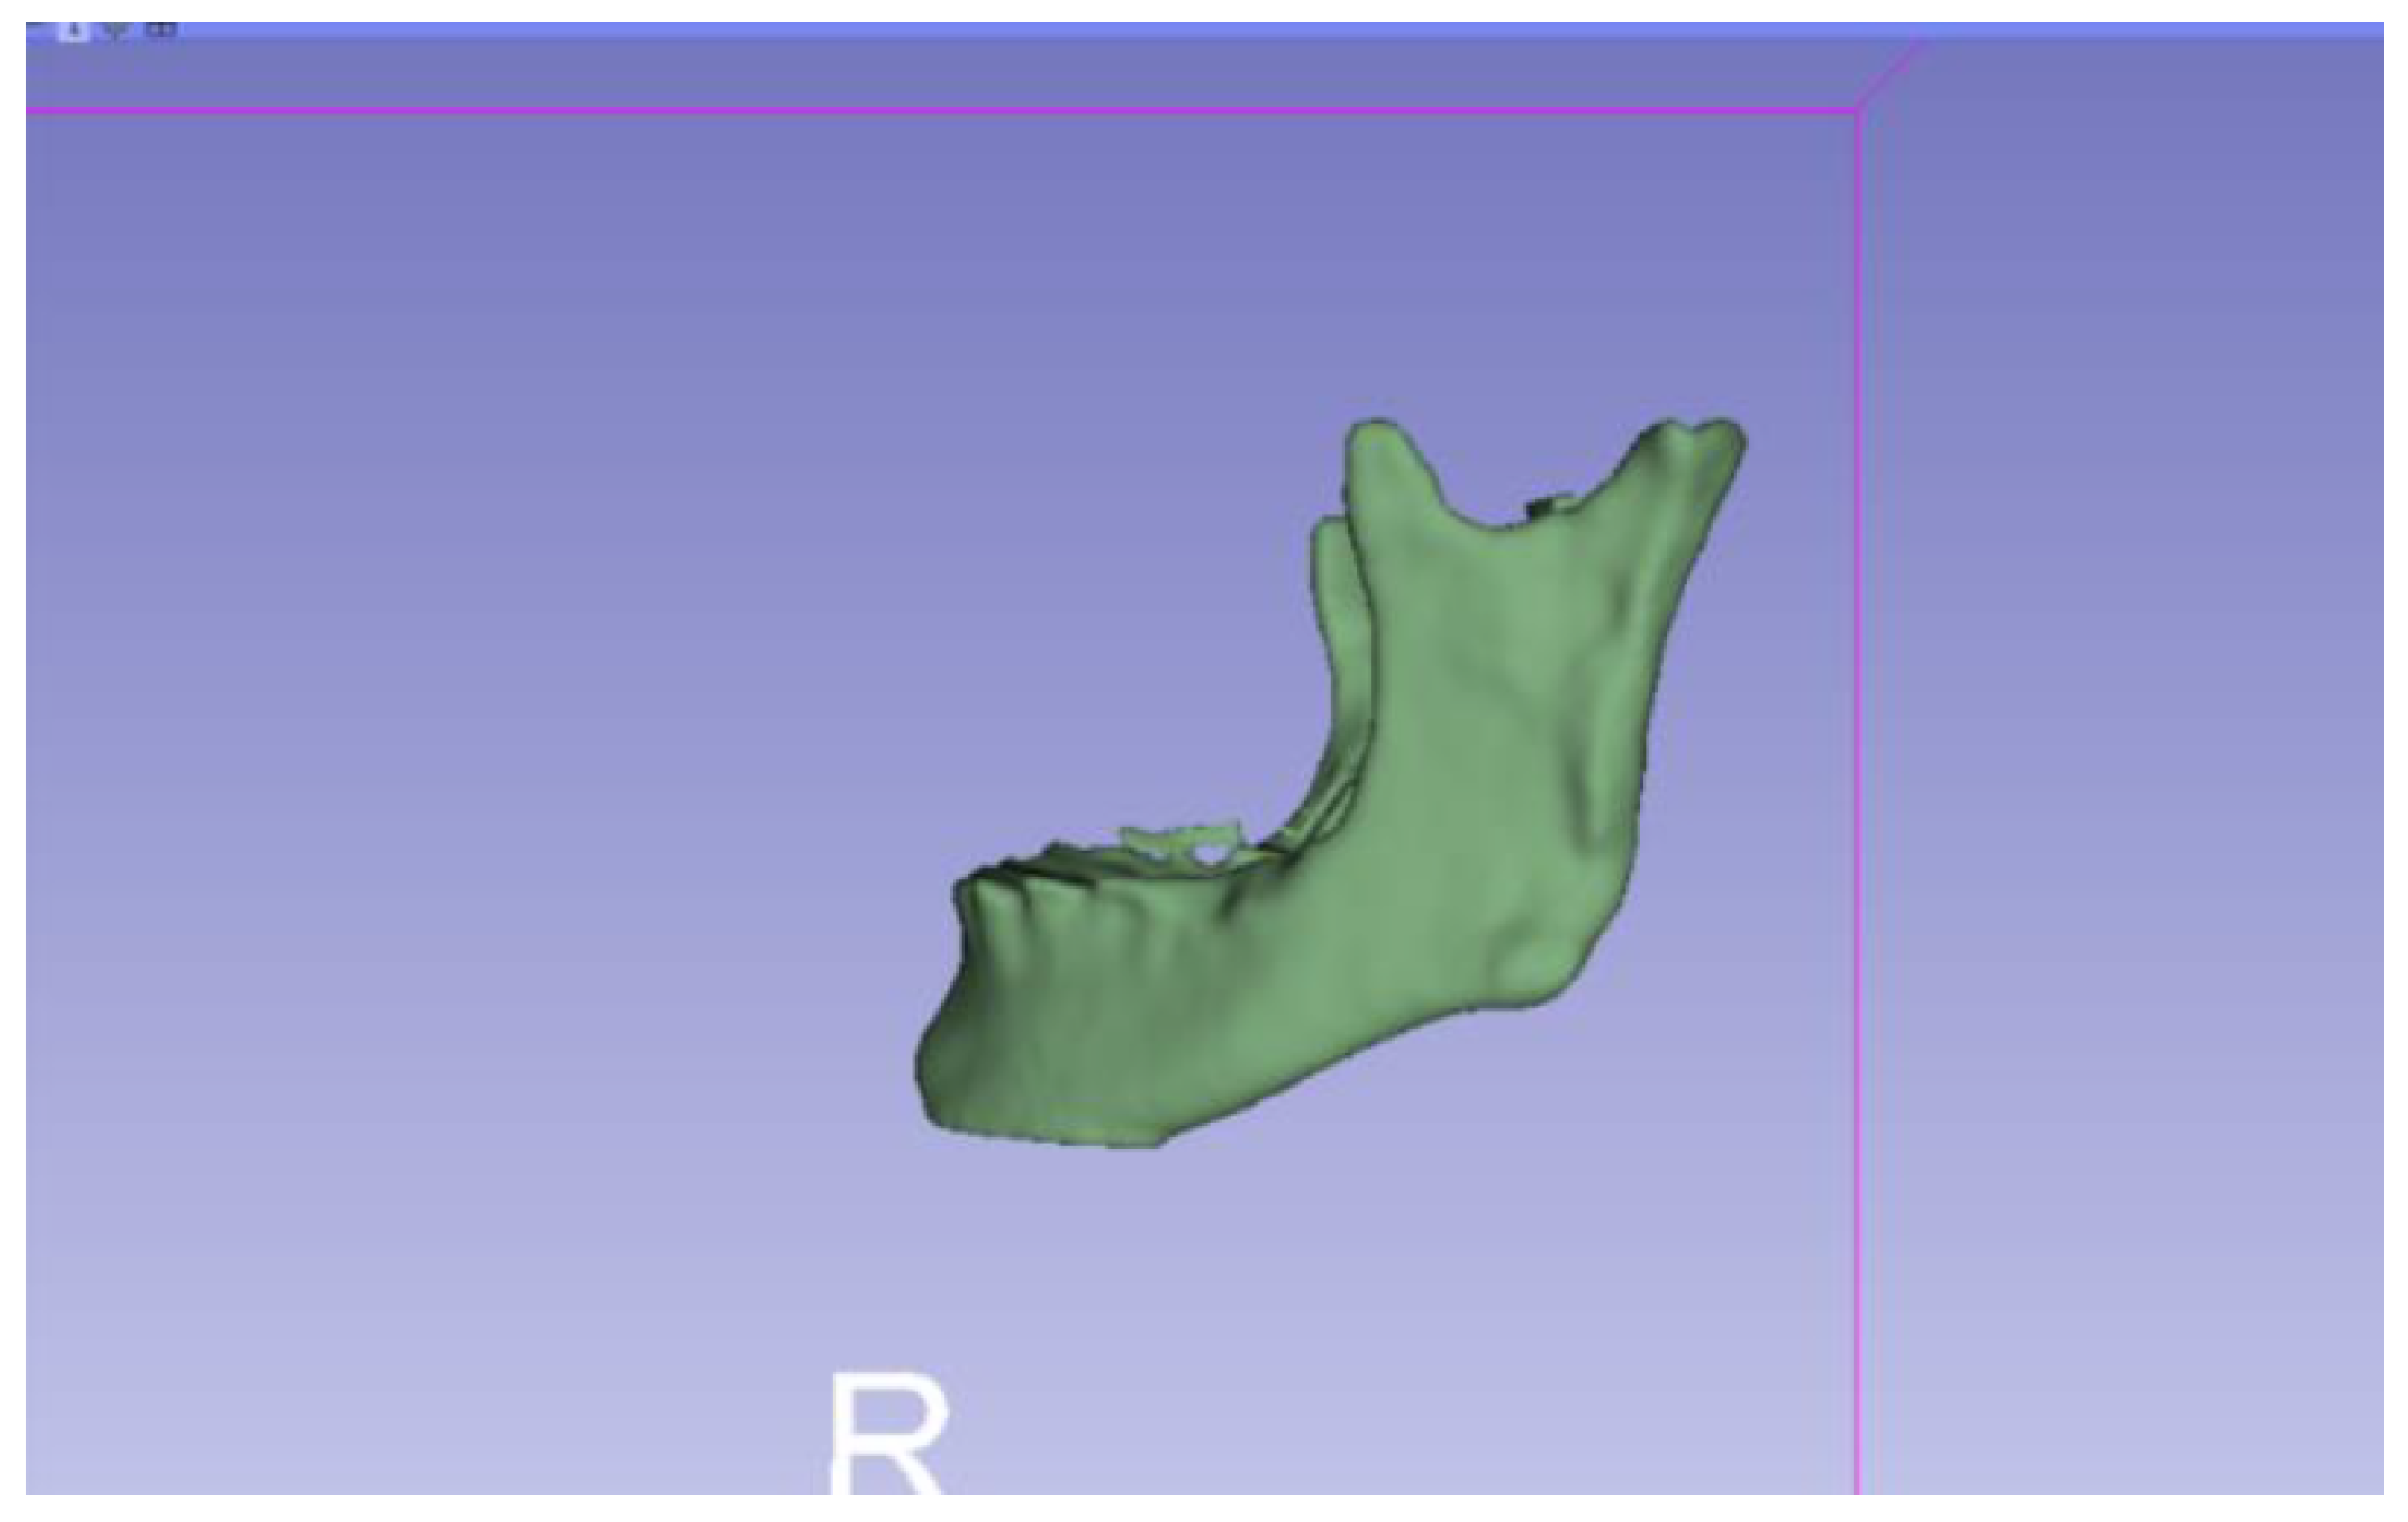

3.2. Human Lower Jaw

3.2.1. DICOM-to-STL Files